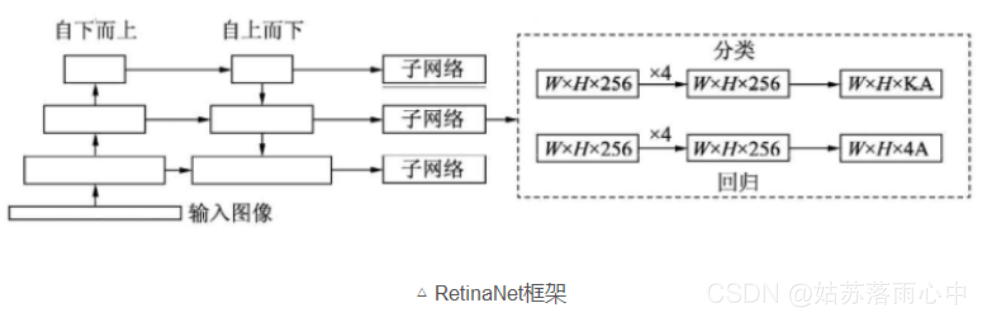

RetinaNet = FPN + sub-network + FL

文章提出了一个基于单个模型的解决方案,该模型集成了多个checkpoints。该模型使用了在ImageNet 上经过预训练的SE-ResNext101作为主干网络,整体网络框架使用的是 RetinaNet SSD。

RetinaNet的框架整体是ResNet+FPN+FCN,它使用ResNet作为backbone来提取图像特征,然后从中抽取5层特征层来构建特征金字塔网络(FPN: feature pyramid network),最后接两个独立的**全卷积网络(FCN: full convolution network)**分别得到物体的类别信息和位置框信息。

对于RetinaNet的网络结构,有以下5个细节:

- 在Backbone部分,RetinaNet利用ResNet与FPN构建了一个多尺度特征的特征金字塔。

- RetinaNet使用了类似于Anchor的预选框,在每一个金字塔层,使用了9个大小不同的预选框。

- 分类子网络:分类子网络为每一个预选框预测其类别,因此其输出特征大小为KA×W×H, A默认为9, K代表类别数。中间使用全卷积网络与ReLU激活函数,最后利用Sigmoid函数输出预测值。

- 回归子网络:回归子网络与分类子网络平行,预测每一个预选框的偏移量,最终输出特征大小为4A×W×W。与当前主流工作不同的是,两个子网络没有权重的共享。

- Focal Loss:与OHEM等方法不同,Focal Loss在训练时作用到所有的预选框上。对于两个超参数,通常来讲,当γ增大时,α应当适当减小。实验中γ取2、α取0.25时效果最好。